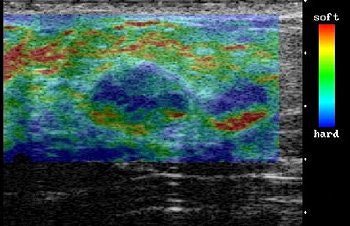

The region of interest (ROI) on elasticity images was drawn to include subcutaneous fat at the top and pectoral muscle at the bottom. Lateral boundaries were set more than 5 mm from the lesion's boundary. Under CAM, each pixel of the elasticity image was assigned one of 256 colors with red representing the greatest strain, blue the least amount of strain, and green the average in the ROI. The color patterns were then scored from 1-5, with the latter indication no strain in the entire hypoechoic lesion.

The final pathologic diagnosis was 59 benign lesions, according to the results. The group found that the mean elasticity score was significantly higher for malignant lesions (4.2) than for benign ones (2.1). Of the malignant lesions, 86% had a CAM score of 4 or 5. Of the benign lesions, 68% had a CAM score of 1 or 2.

![]() |

| On elasticity image, hypoechoic lesion shows mosaic pattern of green and blue. Figure 3. Ako Itoh A, Ueno E, Tohno E, et al, "Breast Disease: Clinical Application of US Elastography for Diagnosis" (Radiology 2006;239:341-350). |